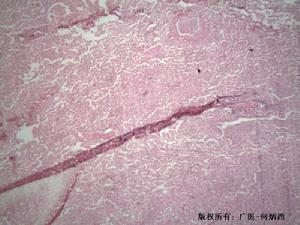

1.腎活檢光鏡檢查

(1)腎血管:LPHS的病理主要表現在腎內血管,常見有動脈壁透明樣變性、類似動脈粥樣硬化的損傷、內膜增生或呈洋蔥皮樣改變。個別病例有微動脈瘤。靜脈彈性纖維組織也可見變性。

(2)腎單位:腎小球輕度系膜增生、局灶硬化、腎小球囊肥厚,間質呈斑點狀纖維化,腎小管輕度萎縮。亦有的患者除腎內血管外,組織學檢查正常。

2.免疫螢光檢查受侵犯的血管有顯著的C3沉積,亦有報導有C4沉積者。當然,C3在血管壁的沉積是一種非特異性改變,可見於許多動脈病變。Miller等在一位48歲的LPHS女患者首次發現腎內小動脈有備解素(properdin)和補體C5b-9、C3沉積,提示補體被激活。腎小球內未見免疫球蛋白沉積。電鏡檢查電鏡檢查未發現特異性病理改變。